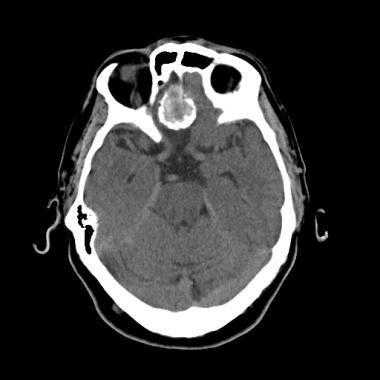

Опухоль головного мозга — глиобластома. Компьютерная томография (КТ). Синяя звездочка в центре обозначает зону центрального некроза опухоли, заполненную жидкостью. Желтые стрелки — окружающий мягкотканный компонент опухоли. Красные звездочки — перифокальный отек мозга. Наблюдается смещение срединных структур и угроза нисходящего транстенториального вклинения мозга.

Проявления опухоли на КТ-сканах без контрастного усиления включают неоднородное образование с нечеткими краями; внутренние области низкой или жидкостной плотности являются очагами некроза (представлены более, чем в 95% МФГ); внутренние области высокой плотности, являющиеся очагами геморрагии или, реже, кальцификациями (они более характерны в тех случаях, когда МФГ является результатом трансформации из астроцитомы низкой степени злокачественности); и значительный масс-эффект и отек (возогенная природа отека).

Исследование КТ с контрастным усилением значительно увеличивает выявление таких признаков, как неровные контуры образрвания, неоднородность, возможное кольцевидное контрастное усиление в периферических отделах патологической зоны.